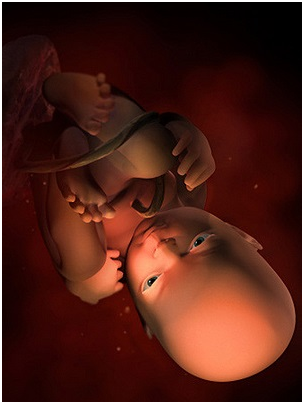

怀孕第34周此时胎儿已经为分娩做好了准备,将身体转为头朝下的姿势。你最近会感觉有一点儿累,这...

怀孕第34周此时胎儿已经为分娩做好了准备,将身体转为头朝下的姿势。你最近会感觉有一点儿累,这... -